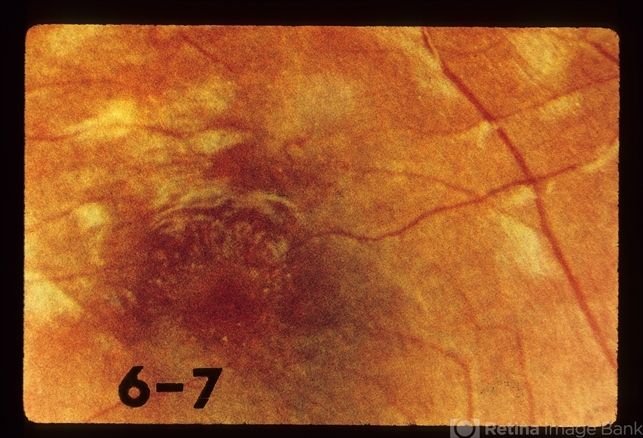

- Condition/keywords

- toxocara canis, worm

- Worm GONE.